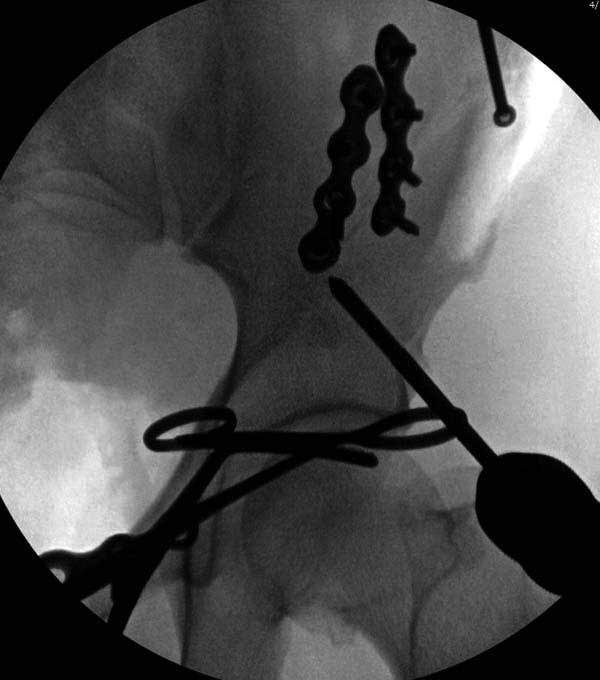

Представлены снимки техники проведения стержней. Через место прикрепления прямой мышцы в Inferior Iliac Spine в направления вырезки создается жесткость. Weber clamp изнутри таза для репозиции, и фиксация после репозиции перелома крыла подвздошной кости. Наружный аппарат удален, нагрузка предполагается через два месяца.